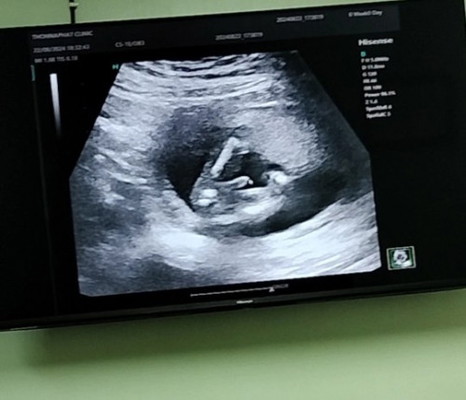

ทีมกุมภาเห็นเพศกันยังค่ะ

คนแรกชายคนสองโชว์จู๋มาแล้วๆเลย 😆

กุมภาพันธ์เหมือนกันค่ะ คนแรกชาย คนสองหมอเห็นจู๋ๆๆแล้ว แม่อยากได้ผญ สงสัยต้องรอคน3 ไม่รู้จะสมหวังหรือป่าว

กุมภาเหมือนกันค่ะ หมอบอก ค่อนไปทางผญ ค่ะ แต่ยังไม่ชัวร์เท่าไหร่ น้องเล่นท่ายากตลอดเลย

บ้านนี้ไปหาหมอมาเมื่อวาน เหมือนจะเป็นจู๋เหมือนกันคะ อิแม่อยากได้ผญ 😂